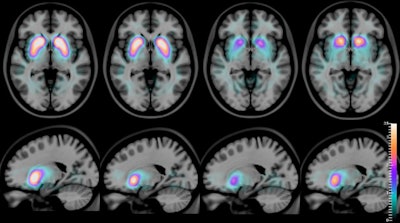

SPECT images, superimposed on an MR atlas, of an axial slice (top row) and a sagittal slice (bottom row) of the human brain, with a quantitative artificial-color scale showing the differences in the average distribution of the radioactive compound [I-123] FP-CIT in the striatum of healthy controls, Alzheimer's disease, dementia with Lewy bodies, and Parkinson's disease (from left to right). Images courtesy of Francisco Oliveira and the Champalimaud Centre for the Unknown.For the first time, autopsies confirm the SPECT images not only differentiate dementia with Lewy bodies from Alzheimer's Disease but also from Parkinson's disease, according to the authors. They also hope that eventually their technique will help to differentiate Parkinson's disease patients with dementia from dementia with Lewy bodies patients.